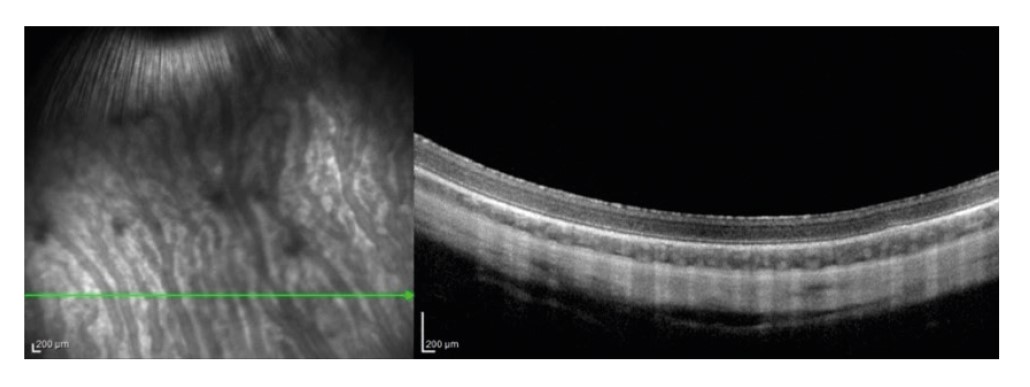

На ОКТ-снимке представлен горизонтальный срез здоровой сетчатки кролика до проведения трансплантации (рис. 1). При анализе снимков ОКТ у кроликов с интактным РПЭ (I группа) на 14-е сутки профиль сетчатки не был изменен, все слои дифференцировались, под нейросенсорной сетчаткой визуализировалась зона умеренной гиперрефлективности, соответствующая локализации трансплантированных клеток.

Рисунок 1. ОКТ-снимок здоровой сетчатки кролика, горизонтальный срез

Примечание. Объяснение в тексте статьи.

Figure 1. OCT image of a healthy rabbit retina, horizontal slice

Note. Explanation in the text of the article.

К 28-м суткам наблюдения и более отмечалось снижение выраженности гиперрефлективности монослоя под нейросенсорной сетчаткой, что скорее всего свидетельствует о распределении клеточного материала, профиль и структура сетчатки оставались неизменными.